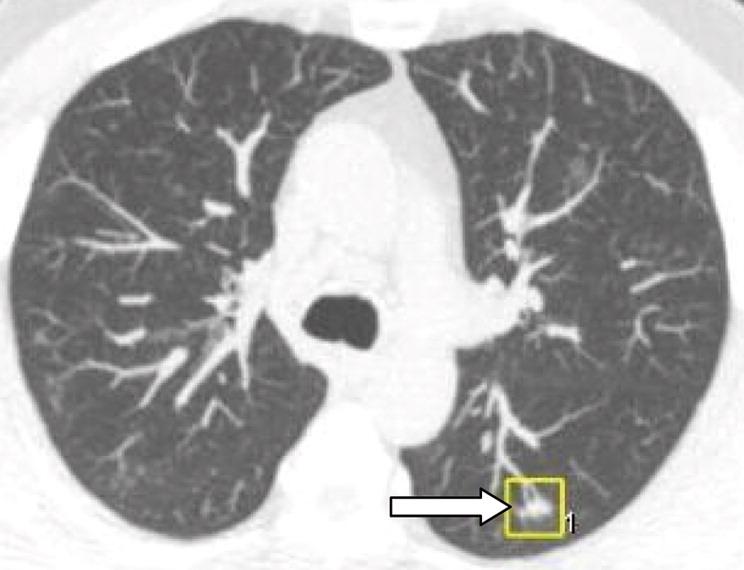

Though most do not resolve, 75% of those that do resolve can be identified at 3-month repeat CT

The rate and speed of disappearance higher for larger nodules (>= 8 mm)

However, rate of malignancy also higher